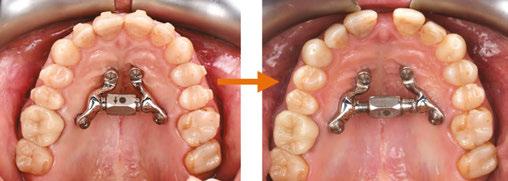

In my practice at Teeters Orthodontics in Peoria, Arizona, I have fully integrated Angel Aligner into my treatment protocols. One of the key innovations I utilize is the angelButton™, a unique feature designed to enhance sagittal bite correction and correct crossbites more efficiently and effectively. By incorporating these built-in buttons with elastics, I am able to achieve more predictable and efficient outcomes for my patients, improving their overall bite alignment with greater precision.